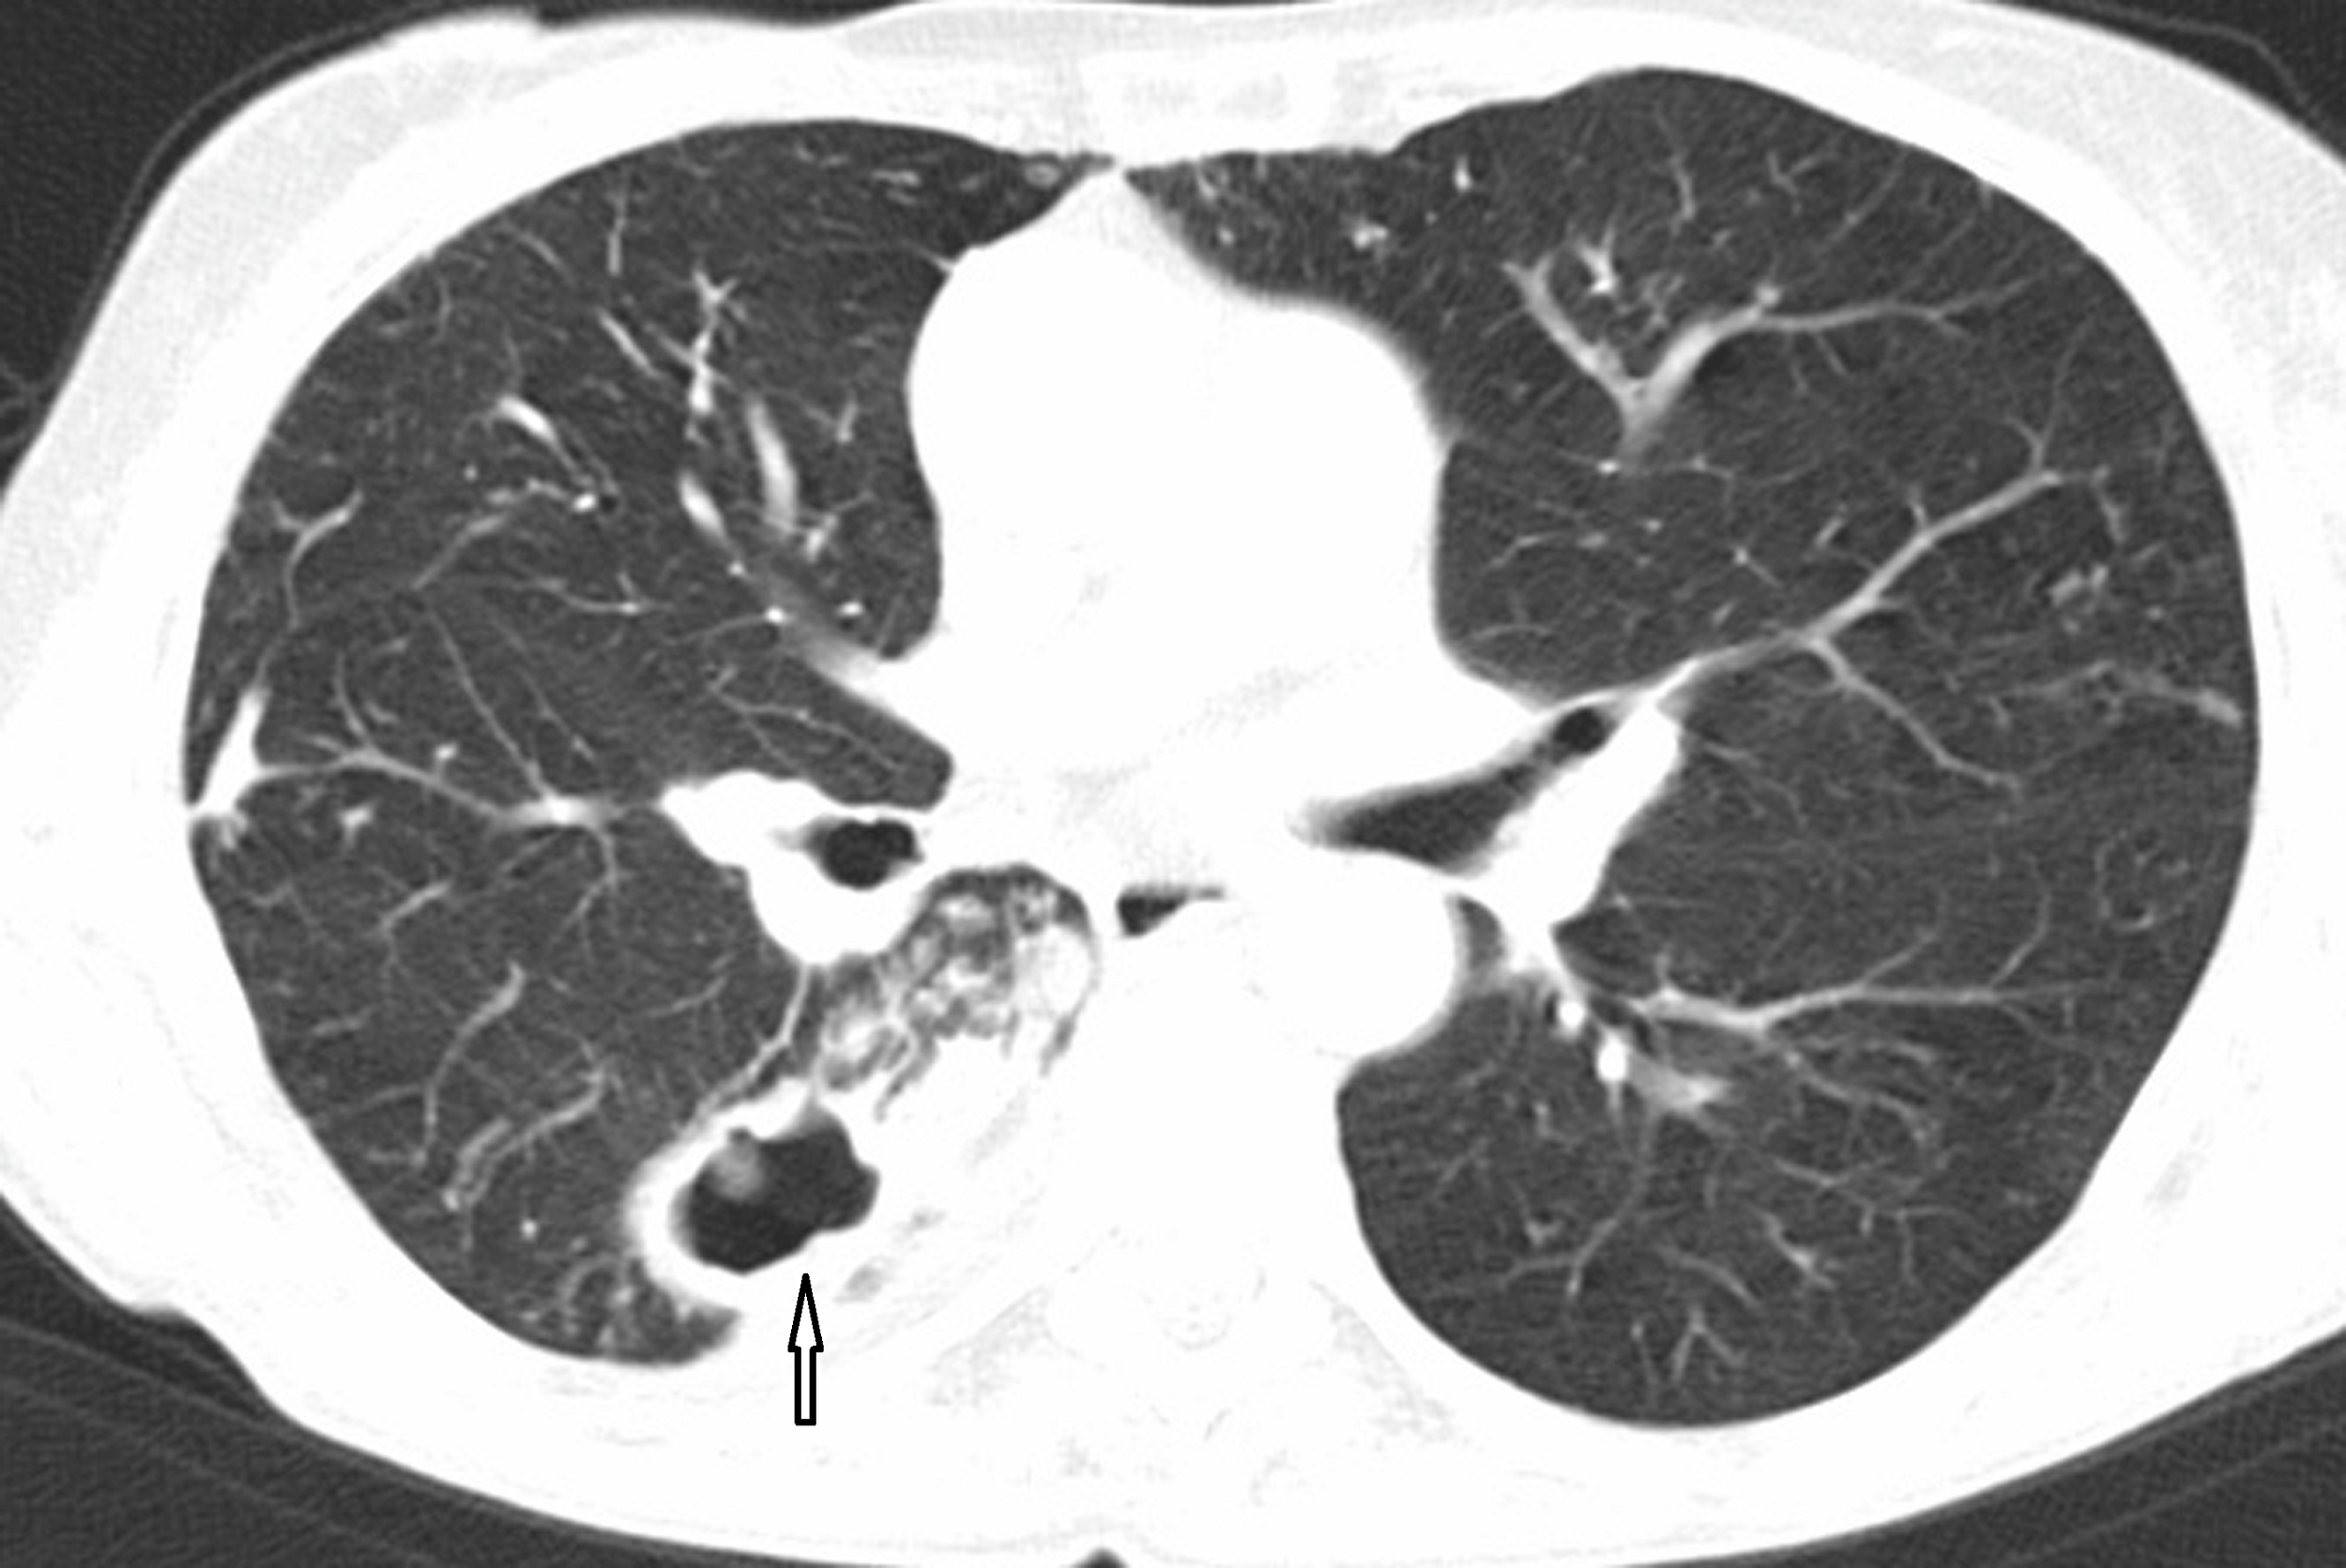

Sie sind die Cousins und Cousinen der Tuberkulosebakterien und können – müssen aber nicht – Infektionskrankheiten beim Menschen hervorrufen. Um sie von den Tuberkulosebakterien abzugrenzen, nennt man sie „Nicht-tuberkulöse Mykobakterien“ kurz NTMs. Annähernd 200 verschiedene Arten und Unterarten sind bekannt. Betroffen sind vor allem Patientinnen und Patienten mit sog. Bronchiektasen (Erweiterung der Atemwege). Zu den häufigsten Erregern gehören Mycobacterium avium complex, Mycobacterium kansasii, Mycobacterium xenopi und Mycobacterium abscessus. Anders als bei Tuberkulose ist eine Ansteckungsgefahr bei den nicht-tuberkulösen Mykobakterien praktisch nicht bekannt. Nicht selten kommt es zu chronischen Verläufen der Infektion.